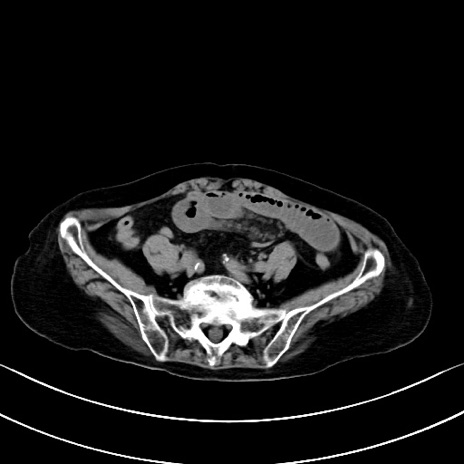

横断像

他院CT